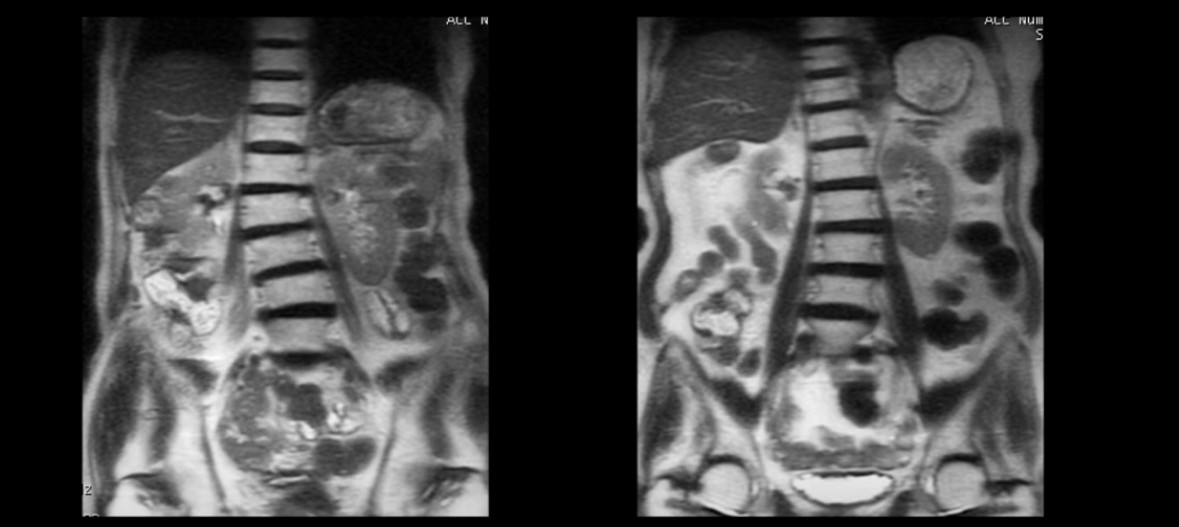

모든 협착증 환자는 예외 없이 근육이 뭉치고 굳어 있고 뒤틀려 있는 문제를 가지고 있습니다. 이걸 가장 쉽게 확인하는 방법은 본인의 MRI나 X-ray를 확인해 보는 것입니다. 특히 70세 이상의 협착증 환자의 척추를 보면 전부 다 휘어지고 틀어져 있습니다.

이 말은 한쪽 근육은 뭉치면서 짧아지고 또 다른 한쪽 근육은 늘어나는 등 심한 불균형이 있다는 얘기입니다. 이렇게 근육이 안 좋으면 신경이 더 눌리고 협착증 증상이 악화됩니다. 하지만 아직도 많은 협착증 환자들이 이런 근육의 중요성을 모르고 아프니까 신경주사만 맞고 있습니다.